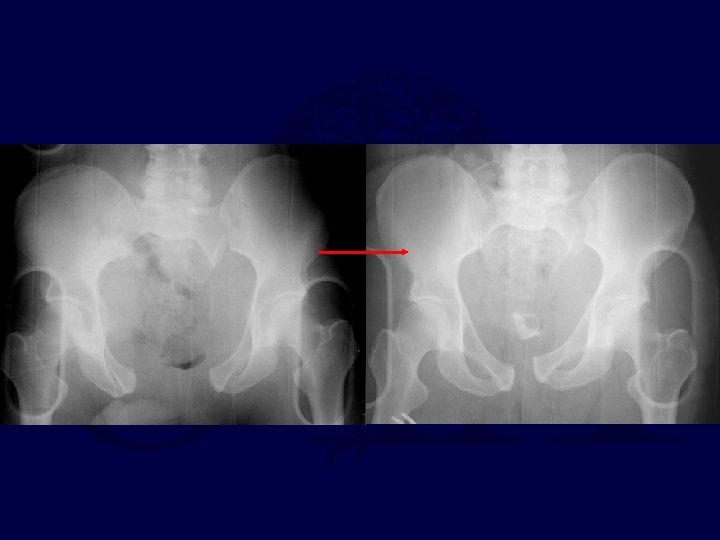

Sheet Application Before

After